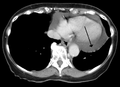

Pericardial effusion etiologies have changed over time and vary greatly depending on geography and the population in question. When pericardial effusion is suspected, echocardiography usually confirms the diagnosis and allows assessment for signs of hemodynamic instability. Cross-sectional imaging with computed tomography (CT) can help to localize and quantify (as in a loculated effusion) or assess for pericardial pathology (pericardial thickening, constrictive pericarditis).[4]

A CT scan image showing a pericardial effusion